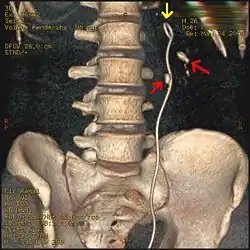

A ureteral stent (pronounced you-REE-ter-ul), or ureteric stent, is a thin tube inserted into the ureter to prevent or treat obstruction of the urine flow from the kidney. The length of the stents used in adult patients varies between 24 and 30 cm. Additionally, stents come in differing diameters or gauges, to fit different size ureters. The stent is usually inserted with the aid of a cystoscope. One or both ends of the stent may be coiled to prevent it from moving out of place; this is called a JJ stent, double J stent or pig-tail stent.

[1]Ureteral stents are used to ensure the openness of a ureter, which may be compromised, for example, by a kidney stone or a procedure. This method is sometimes used as a temporary measure, to prevent damage to a blocked kidney, until a procedure to remove the stone can be performed. Indwelling times of 12 months or longer are indicated to hold ureters open, which are compressed by tumors in the neighbourhood of the ureter or by tumors of the ureter itself. In many cases these tumors are inoperable and the stents are used to ensure drainage of urine through the ureter. If drainage is compromised for longer periods, the kidney can be damaged.